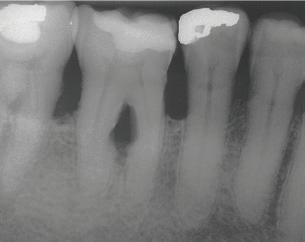

Stage IV –Severe Periodontitis

The American Academy of Periodontology (AAP) released a comprehensive update for the classification and documentation of periodontal and peri-implant diseases and conditions. This comprehensive update was developed and implemented because of the overwhelming information confirming the link between oral health and whole-body health. The first update the dental profession has seen since 1999, the updated classifications include a framework for staging and grading as well as defining the distribution of disease.

The staging consists of the severity of the disease and the complexity for disease management, while the grading defines the rate of progression, a patient’s overall health, social habits, and the expectation of how well the disease will respond to treatment. Distribution expresses if the disease is localized or generalized.

This new classification and documentation of periodontal disease takes into consideration a patient’s current oral condition, health history, and risk factors. This information helps assess how serious an infection in the gingival tissue and underlying bone can be for a patient’s oral health and whole-body health.

THE AMERICAN ACADEMY OF PERIODONTOLOGY UPDATES DISEASE CLASSIFICATIONS

Recognizing and treating periodontal disease in its earliest stages results in better patient outcomes and has been shown to positively affect the long term whole-body health of patients. Early disease recognition and management can only be accomplished by performing a thorough comprehensive exam which includes, but is not limited to, an oral cancer exam, full mouth pocket charting, and radiographs with a clear view of the interdental crestal bone. As clinicians, we know radiographic bone loss, no matter how minor, is a result of a long-standing infection in periodontal tissue.